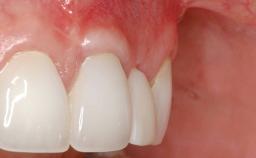

A 30-year-old woman was referred by her general dentist for evaluation of an esthetic complication related to previous implant treatment for congenitally missing maxillary lateral incisors. The patient’s chief complaint was the inadequate esthetic appearance of her smile. The case demonstrates the use of a combined approach to achieve optimal results. Two different flap designs - a tunnel technique and a coronally advanced flap - are employed based on the surgical objectives for the affected site.

Periodontal Plastic Surgery and Prosthetic Procedures to Treat Peri-Implant Soft-Tissue Dehiscences

Soft Tissue Anatomy Intact Defective